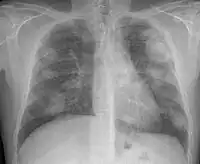

For uncomplicated silicosis, chest x-ray will confirm the presence of small (< 10 mm) nodules in the lungs, especially in the upper lung zones. Using the ILO classification system, these are of profusion 1/0 or greater and shape/size "p", "q", or "r". Lung zone involvement and profusion increases with disease progression. In advanced cases of silicosis, large opacity (> 1 cm) occurs from coalescence of small opacities, particularly in the upper lung zones.

With retraction of the lung tissue, there is compensatory emphysema. Enlargement of the hilum is common with chronic and accelerated silicosis. In about 5–10% of cases, the nodes will calcify circumferentially, producing so-called "eggshell" calcification. This finding is not pathognomonic (diagnostic) of silicosis. In some cases, the pulmonary nodules may also become calcified.

Chest X-ray showing uncomplicated silicosis